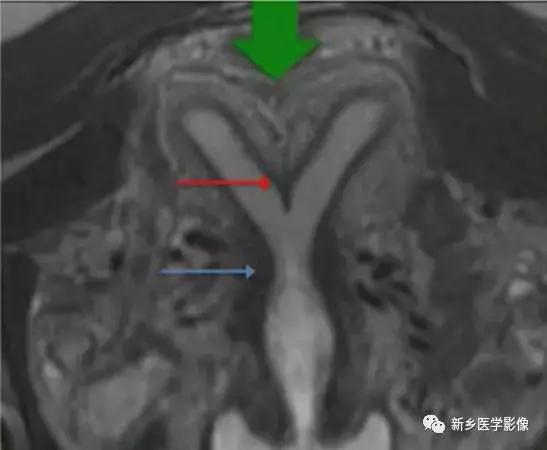

完全型纵隔子宫:短T2信号纵隔贯穿宫腔,宫颈管及阴道上段。

MR诊断为完全型纵隔子宫伴阴道纵隔。

完全型纵隔子宫:宫底平坦,纵隔贯穿宫腔和宫颈